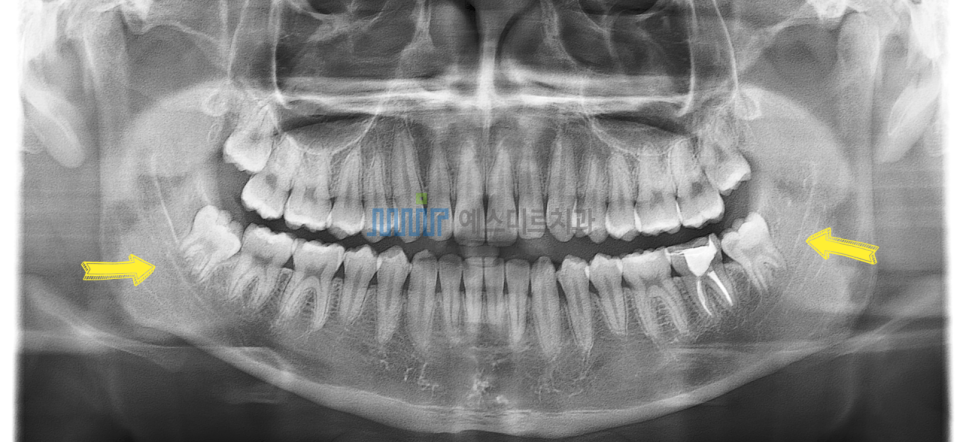

아래 사랑니 발치 전

사랑니 발치 후에도 턱뼈는 변하지 않아요

특히 매복 사랑니는

단순히 '빼는 것'이 아니라

주변 치조골과 신경을 보호하면서

안전하게 제거하는 과정이 중요합니다

사랑니 발치 시 중요한 포인트!

✔ 필요한 범위 내에서만 뼈를 삭제하고

주변 조직을 최대한 보존하는 발치

✔ 신경과의 거리·위치를 정확히 확인한 후 진행하는 정밀 진단

(필요 시 3D CT 촬영을 통해 안전 범위를 평가합니다.)